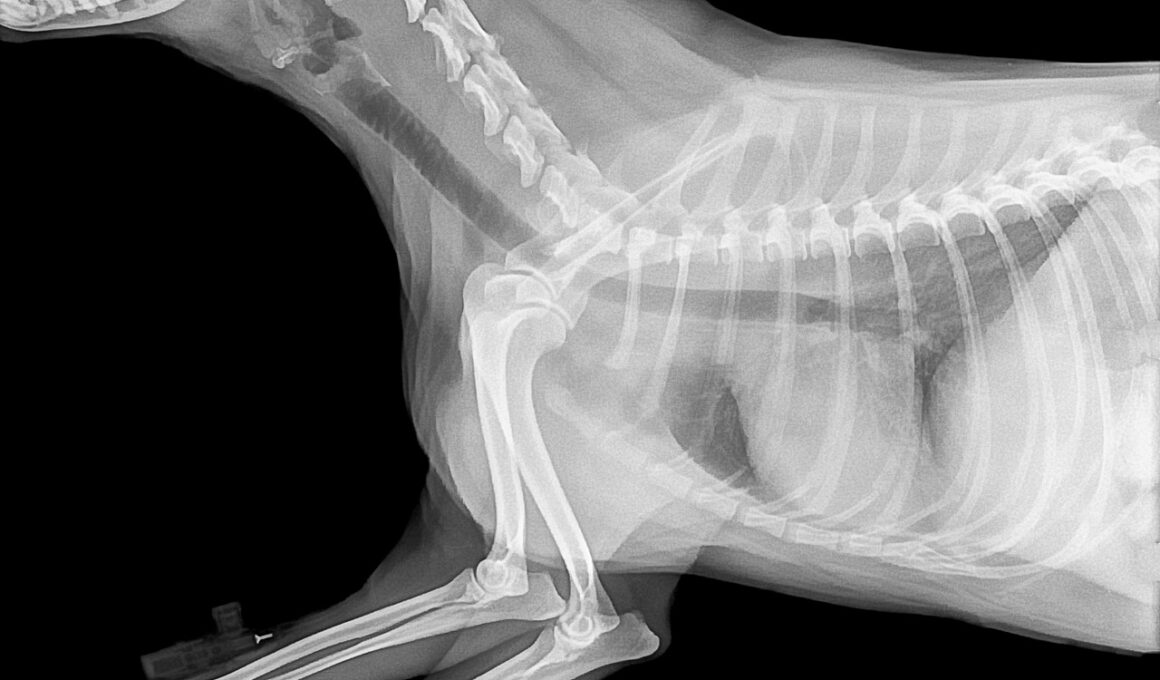

Before splinting a broken bone in your pet, having the right materials is essential. Using items in your home can make a significant difference in the splinting process. Some common materials include cardboard, wooden sticks, or commercially available splints designed for pets. Make sure that any material you choose is rigid enough to provide support yet flexible enough not to cause injury. The padding is equally important; this can be achieved with soft towels or cloth to prevent your pet’s skin from being irritated by the splint. A good combination of materials will help create a well-supported splint that minimizes discomfort. Additionally, keep a roll of cohesive bandage or soft tape handy for securing the splint in position. Avoid using adhesive tape that could damage the pet’s fur or skin. When preparing your supplies, clean them with appropriate disinfectants to reduce the risk of infection. Have sterile wipes or antiseptic available to treat any open wounds. Finally, familiarize yourself with the anatomical structure of your pet’s limb to enhance your effectiveness and confidence during the procedure.

Fitting the splint requires attention to detail and technique. Placing the splint incorrectly can lead to improper healing or further injury. Start by ensuring that the splint covers the joint above and below the fracture; this helps immobilize the area effectively. Do not rush this crucial step, and take your time to ensure proper alignment. The next step is to wrap the padding around the bones and joints before applying the splint. Always check for signs of swelling or restricted blood flow after placing the splint. Loose splints may shift or fall off altogether, while tight splints can cause serious harm. Adjusting your technique according to the size and breed of your pet is essential. Always maintain a calm atmosphere to avoid startling them, which may lead to sudden movements causing further injury. It may be helpful to have a friend assist you. Following these guidelines can make a vital difference for your pet’s recovery while strengthening their trust in you as a caregiver.